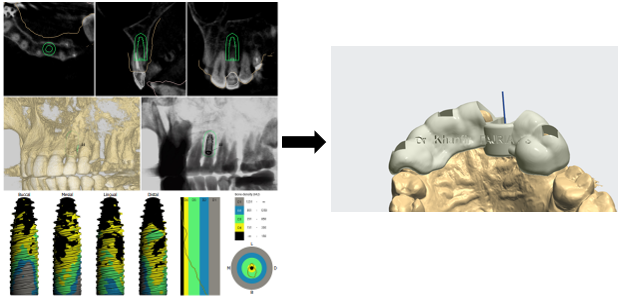

After scaling and root planing with hygiene motivation, we took a bimaxillary digital impression of the patient (Figure 3) and planned a tooth-supported surgical guide based on the complementarity between the STL file from the digital impression and the DICOM file from the CBCT (Figure 4, Figure 5).

Figure 4. Modeling the provisional prosthesis and selecting the implant axis

Figure 5. Combining STL and DICOM files to create a surgical guide